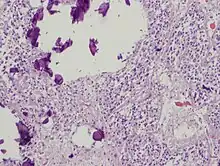

The pineal body in humans consists of a lobular parenchyma of pinealocytes surrounded by connective tissue spaces. The gland's surface is covered by a pial capsule.

The pineal gland consists mainly of pinealocytes, but four other cell types have been identified. As it is quite cellular (in relation to the cortex and white matter), it may be mistaken for a neoplasm.[18]

| Cell type | Description |

|---|---|

| Pinealocytes | The pinealocytes consist of a cell body with 4–6 processes emerging. They produce and secrete melatonin. The pinealocytes can be stained by special silver impregnation methods. Their cytoplasm is lightly basophilic. With special stains, pinealocytes exhibit lengthy, branched cytoplasmic processes that extend to the connective septa and its blood vessels. |

| Interstitial cells | Interstitial cells are located between the pinealocytes. They have elongated nuclei and a cytoplasm that is stained darker than that of the pinealocytes. |

| Perivascular phagocyte | Many capillaries are present in the gland, and perivascular phagocytes are located close to these blood vessels. The perivascular phagocytes are antigen presenting cells. |

| Pineal neurons | In higher vertebrates neurons are usually located in the pineal gland. However, this is not the case in rodents. |

| Peptidergic neuron-like cells | In some species, neuronal-like peptidergic cells are present. These cells might have a paracrine regulatory function. |